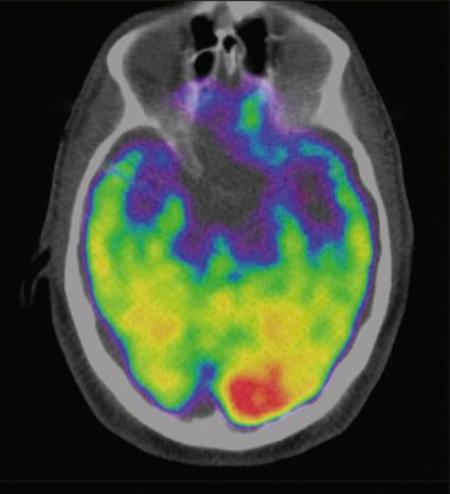

A recent study postulates that people with heightened activity in the amygdala, a region of the brain linked to stress, are at a greater risk of heart disease and stroke. The researchers involved in this discovery said that the study could lead to new methods in the targeting and treatment stress-related cardiovascular problems.

In the recent study, researchers conducted PET/CT body scans on 239 patients to record their brain, bone marrow and spleen activity, and artery inflammation; after which they were tracked for an average of 3.7 years. In this time, 22 patients had cardiovascular ailments including heart attack, angina, heart failure, stroke and peripheral arterial disease. Based on the findings the researchers concluded that those with higher amygdala activity were more likely to have a cardiovascular disease and developed problems sooner than those with lower activity.